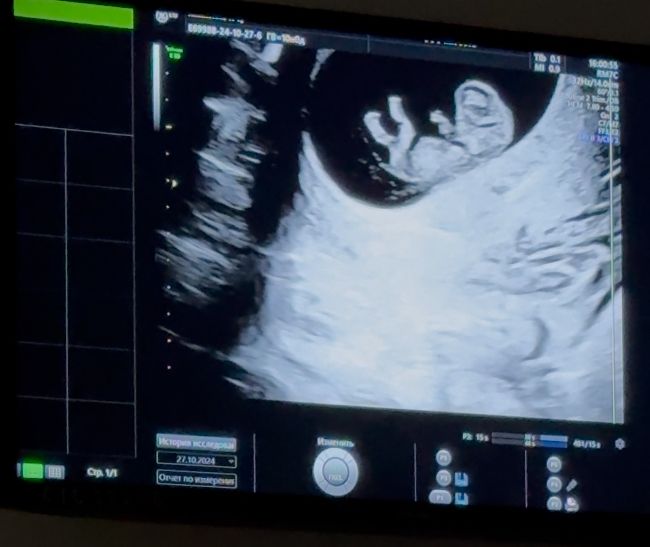

🥰какой интересный) Пузожитель) 🤗